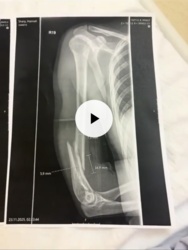

inty★2026-01-10T21:47:55+01:000@Marshalist no to koles musial niezla sile przylozyc ze az zlamal babie lokiec